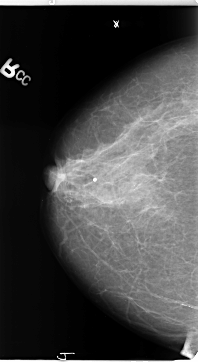

B_3137_1.RIGHT_CC

RIGHT_CC LINES 4704 PIXELS_PER_LINE 2568 BITS_PER_PIXEL 12 RESOLUTION 50 NON_OVERLAY